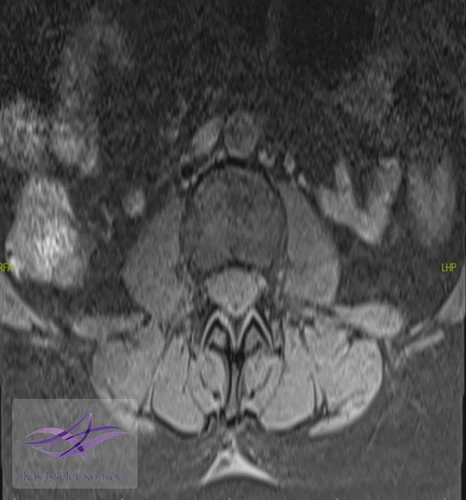

Resim 2. Aksiyel T2 ağırlıklı MR görüntülerinde lezyon paraspinal kas düzlemlerinden net bir şekilde ayrılarak deri altı doku ile fasyal tabaka arasında iyi sınırlı bir sıvı sinyal alanı mevcut.

Morel–Lavallée lezyonu (MLL), subkutan doku ile derin fasya arasındaki ayrılma sonucu oluşan, hemolenfatik sıvı birikimiyle karakterize kapalı dekolman yaralanmasıdır. Trokanter majör çevresi en sık yerleşim yeri olmakla birlikte, lomber bölgedeki yerleşim son derece nadirdir ve diğer yumuşak doku ya da spinal patolojileri taklit edebilir.